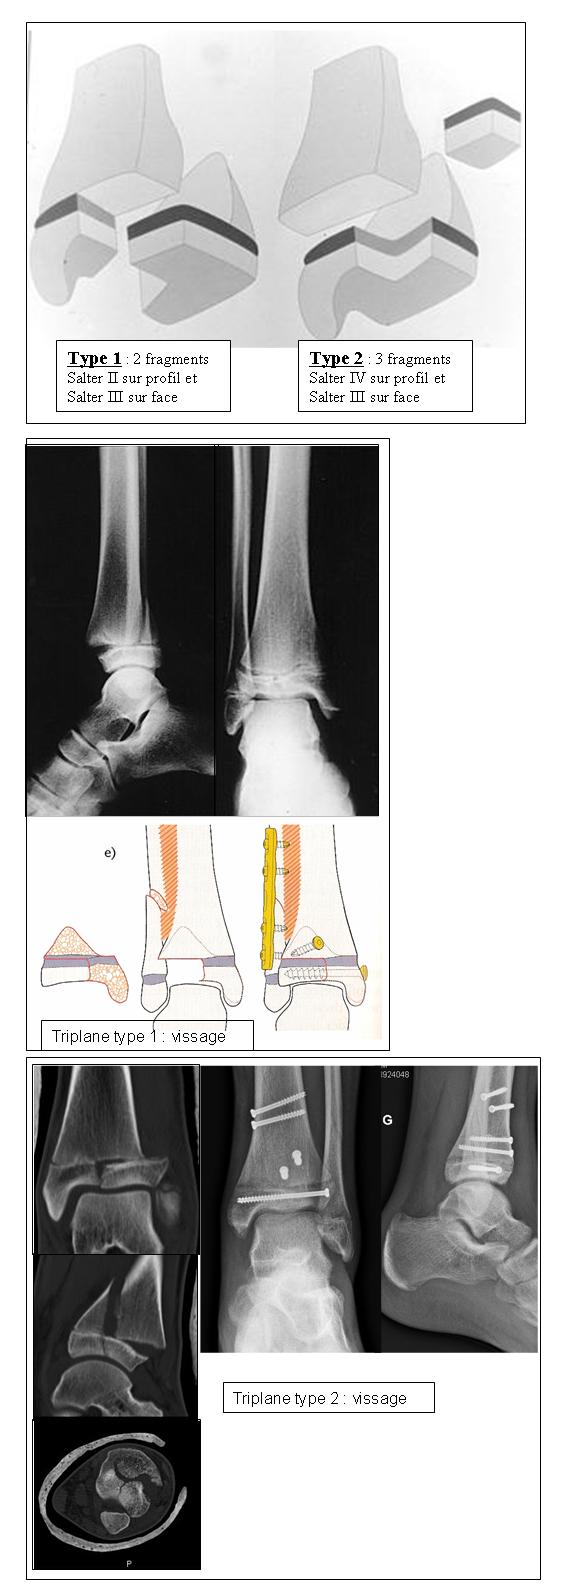

◦ type 1: triplane à 2 fragments

▪ ressemble à un Salter II sur le profil

▪ et à un Salter III sur le face

◦ type 2: triplane à 3 fragments

▪ ressemble à un Salter IV sur le profil

si > 2 mm: R/ chirurgical (réduction ouverte et ostéosynthèse)